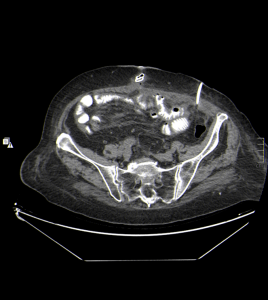

Posteriormente, se realiza un control tras 4 días a partir del momento de la colocación del catéter de drenaje, gracias al cual se obtienen las siguientes imágenes:

Haz click en las imágenes para verlas ampliadas

Se realiza estudio de TC abdominopélvico con contraste oral, se compara con anterior, apreciándose, mejoría, con resolución prácticamente total de la colección de FI izquierda, visualizándose el catéter pig-tail, bien posicionado. No se evidencia dilatación de asas intestinales, se visualiza transito intestinal conservado sin extravasación del contraste.